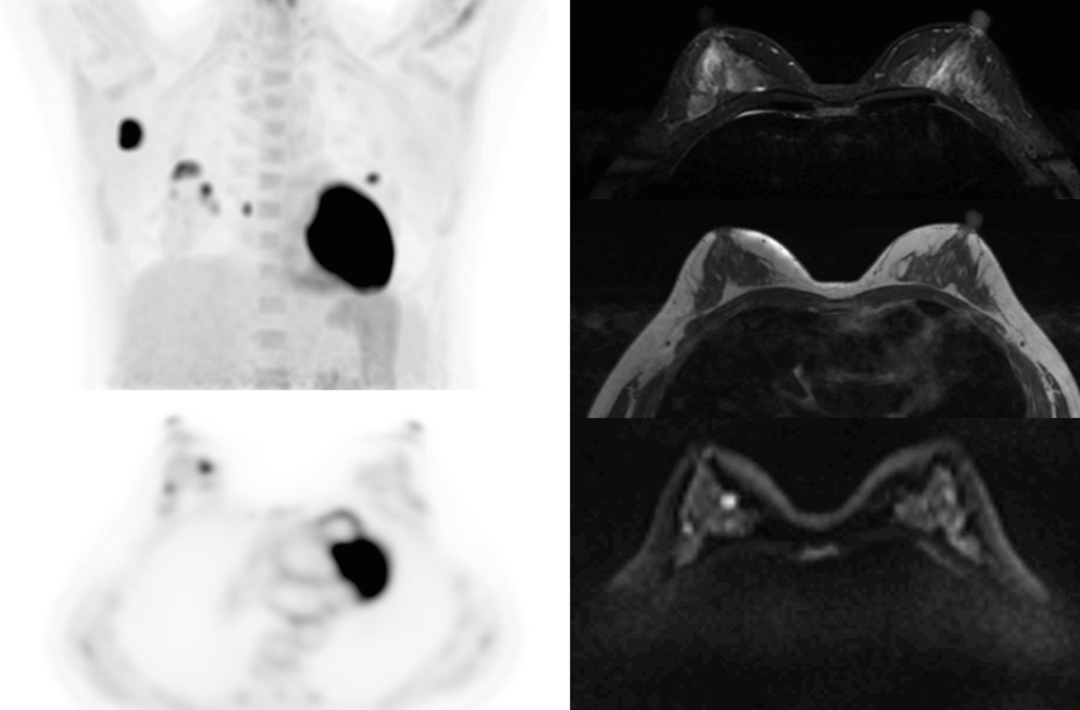

The following are the cases of optimized TNM staging of breast cancer, esophageal cancer, prostate cancer and other diseases under the long axial field of "spatio-temporal integration" ULTRA-clear TOF PET/MR.  Thanks to Capital Medical University Xuanwu Medical Treatment for providing the image.